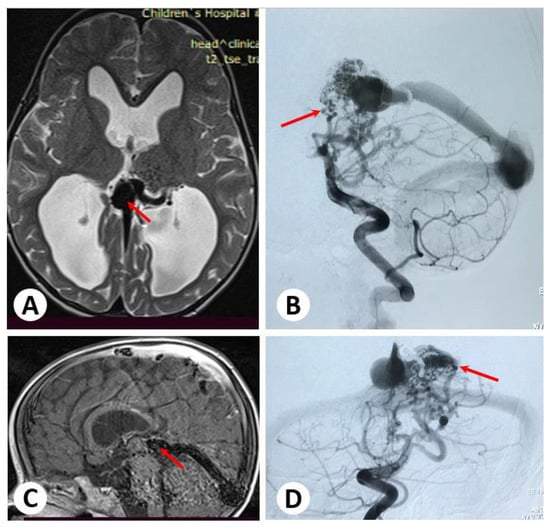

3.1. Illustrative Cases: Case 1

3.2. Illustrative Cases: Case 2